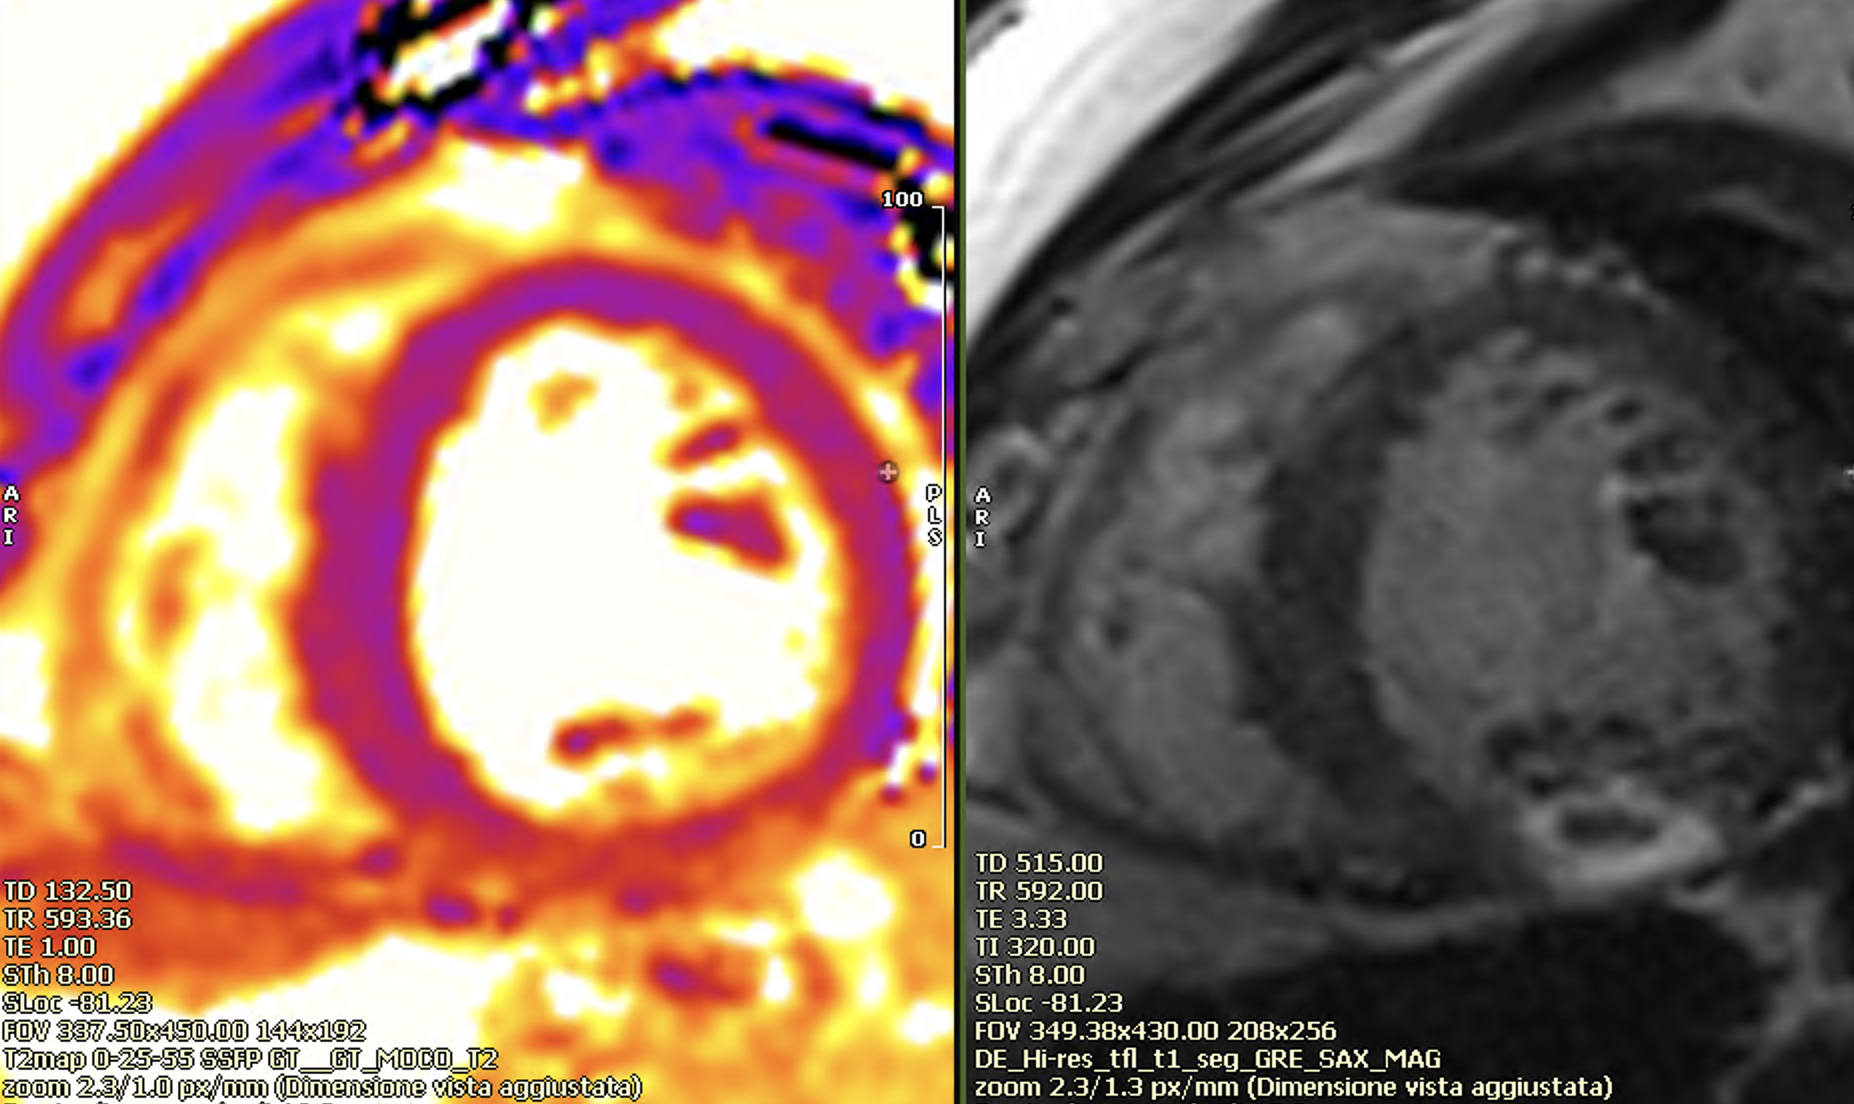

Non ischemic late enhancement (left panel), apical thrombus in early gad sequences (right panel).